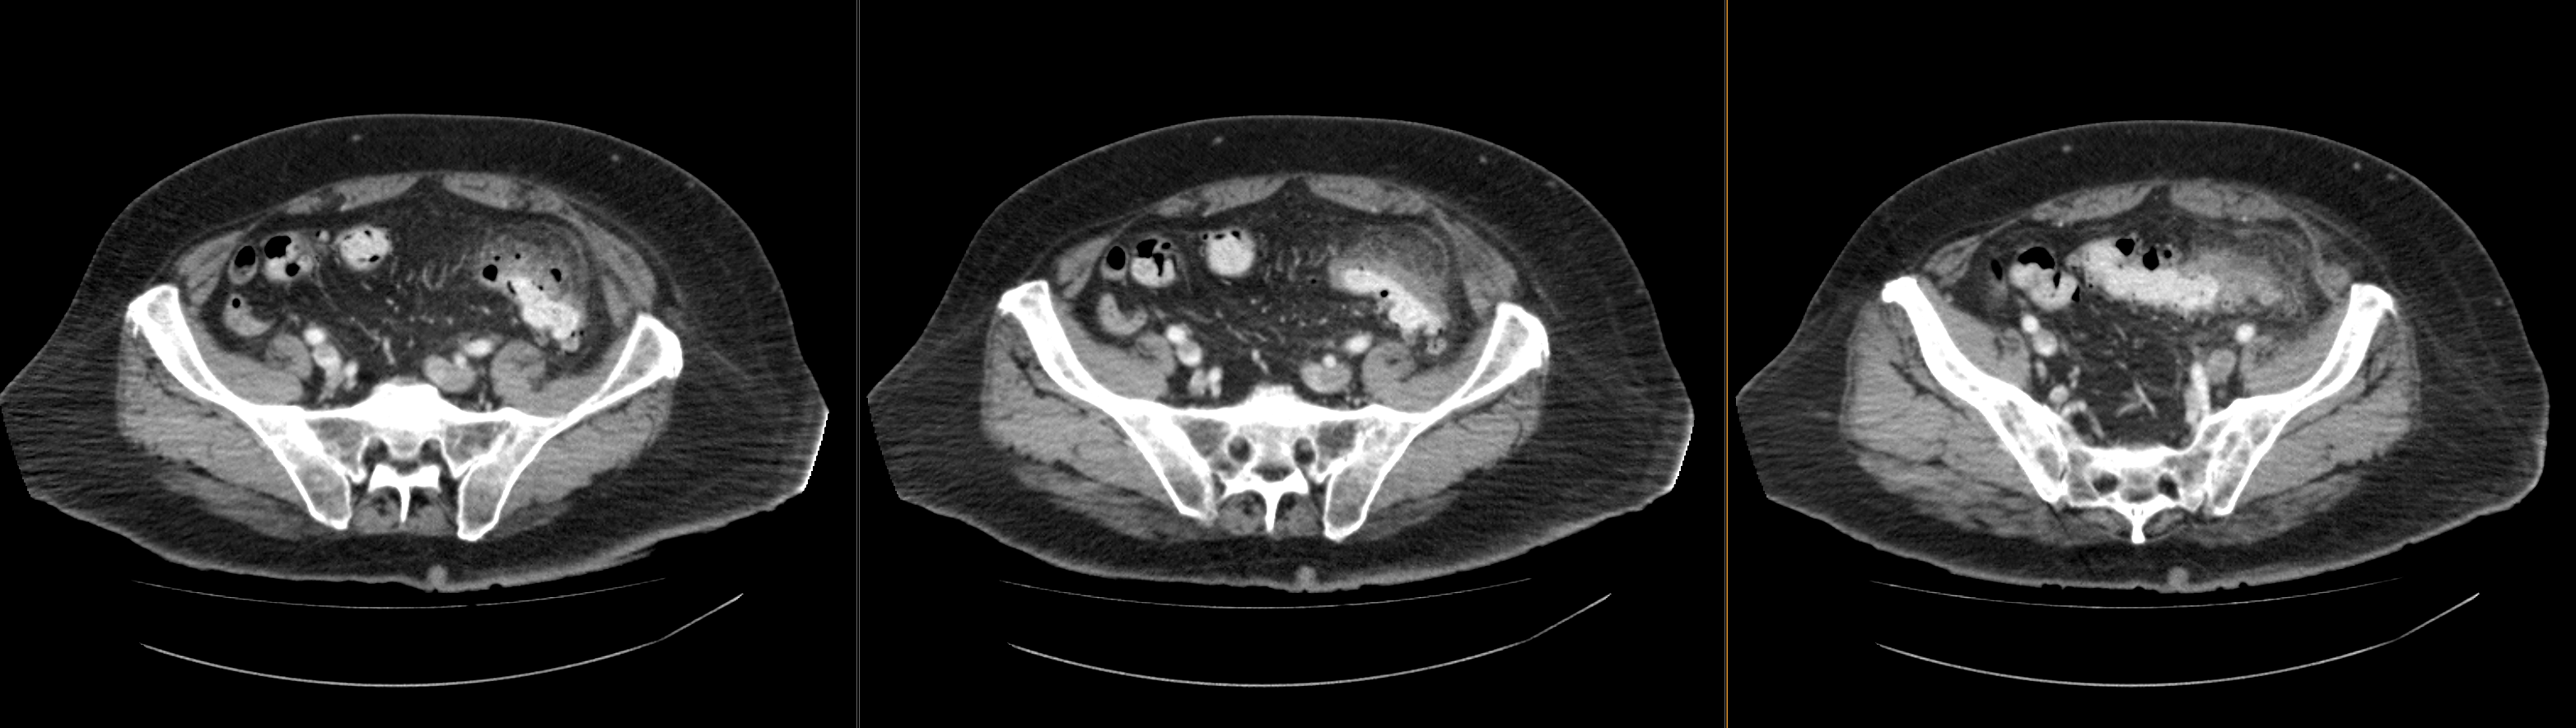

Pertinent Imaging Observations

Click on the links below to view images from the study, and assess these key findings as best you can.

View the full study if you'd like to like a look yourself

There is diverticulosis of the sigmoid colon. The thickening with fat stranding around the sigmoid are indicative of inflammation from diverticulitis. There is no fluid collection to suggest abscess.